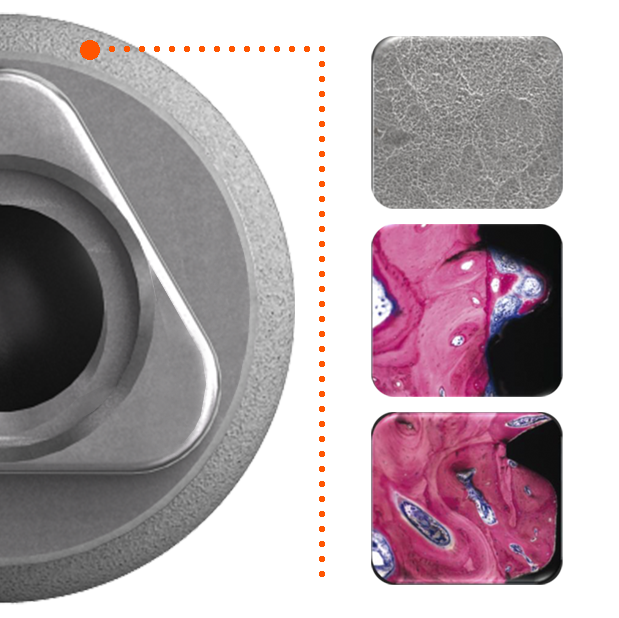

Sur le plan parodontal, la gestion du profil d’émergence a été revisitée de façon à favoriser le réaménagement d’un joint muqueux épais de première intention qui a vocation à jouer le rôle de barrière naturelle.

Le positionnement vertical de l’implant est légèrement modulable selon le biotype parodontal. L’interface prothétique est décalée au dessus du joint muqueux ; le risque de contamination iatrogène lors des phases de restauration prothétique est réduit.